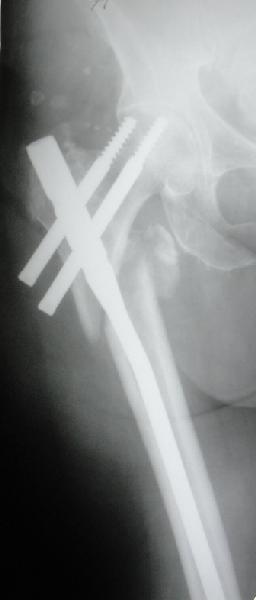

Re: Чрезвертельный перелом бедра

E> На мой взгляд, причиной телескопирования явилось несоответствие

E> диаметра гамма нэйл с диаметром канала подвертельного отдела бедра:

Диаметр гаммы в диафизарной части ~11 мм. А диаметр канала, тем более у пожилых с остеопорозом, может быть мм 15. Даже рассверливать обычно не приходится, после формирования широкого канала в вертельной области можно сразу толкать гвоздь, он влетает, как карандаш в стакан. Так что соответствия диаметров не бывает никогда. Однако представленная ситуация случается далеко не каждый раз. Если гвоздь в центральном отломке входит чуть медиальнее верхушки вертела, и идет вдоль передне-латеральной стенки центрального отломка, то все будет хорошо.

В приложении похожий пример, к счастью, пациентка появилась не после, а "за полчаса" до протрузии. Пересинтезировали с исправлением ошибок.